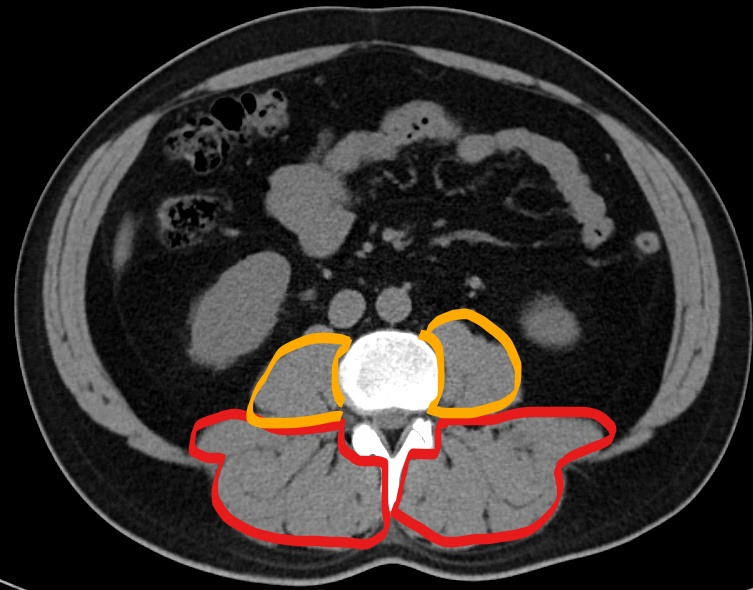

붉은색: 등심, 오렌지색: 안심

등심은 말 그대로, 등에 있어 등심이다. 근육은 수축과 이완 두 가지밖에 할 수 없는데, 주 활동은 이완이 아니라 수축이다. 등심, 그러니까 저 등심이 수축하면, 짧아지면서 등을 꼿꼿이 세우게 된다. 그래서 척추 기립근 (ecector spinae muscle)이라고 한다.

CT상에서 보이는 회색 근육이고, 검은색지방이다. 좌측 사진을 보면 근육 사이사이 검은색 선이 보이는데 지방이다. 물론 사람에서는 그렇고, 소고기에서 이 지방마블링이라 한다.

CT상에서 보면, 이 안심은 복벽 안에 있는 요근(psoas muscle)이다. 이 근육이 수축 시, 허리가 ㄱ 자로 굽어진다. 등심(ecector spinae muscle, 척추 기립근)이 수축하면 허리가 펴지고, 안심(psoas muscle, 요근)이 수축하며 허리가 굽어진다. 등심이 동전의 앞면이라면, 안심은 동전의 뒷면이다.

등심은 복벽 밖에 있고, 길고 두꺼우며, 기름이 많다. 반대로 안심은 복벽 안에 있고, 얇고 가늘며, 기름이 적다. 운동으로 등심(ecector spinae muscle, 척추 기립근)은 부피를 키울 수 있지만, 안심(psoas muscle, 요근)은 키우기 어려워 육질이 훨씬 부드럽니다.